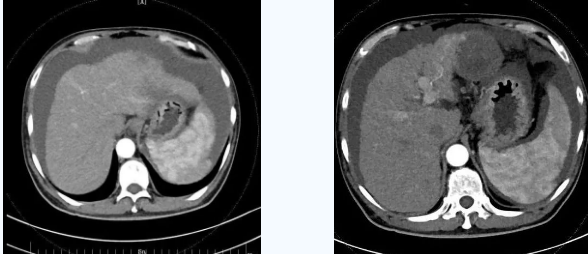

由于大量腹水、晚期肝癌加上尿毒癥等的綜合病癥,手術(shù)難度和危險(xiǎn)系數(shù)都比平常增加了幾倍,面對(duì)這樣的情況,術(shù)前韓國(guó)宏院長(zhǎng)帶著團(tuán)隊(duì)反復(fù)分析討論,全面評(píng)估,在患者的各項(xiàng)指標(biāo)達(dá)到手術(shù)標(biāo)準(zhǔn)后,對(duì)患者實(shí)施了經(jīng)頸靜脈肝內(nèi)門腔靜脈分流術(shù)(TIPS),手術(shù)取得成功,術(shù)后患者恢復(fù)良好。

術(shù)后一個(gè)月秦先生來(lái)院復(fù)查,腹水已明顯較前減少,精神和飲食較術(shù)前明顯好轉(zhuǎn)。